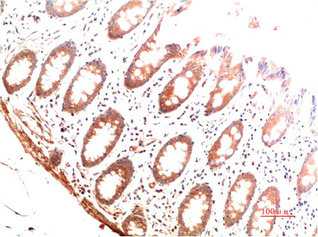

圖片:

產品描述:本產品為COL1A1單克隆抗體(CUSABIO貨號:CSB-MA952416),特異性識別I型膠原蛋白α1鏈(COL1A1),該蛋白是構成細胞外基質的主要成分,在維持組織機械強度、調控細胞黏附和信號傳導中發揮關鍵作用,尤其與纖維化疾病進程、腫瘤微環境重塑及骨代謝調控密切相關。該抗體經嚴格驗證,適用于ELISA和免疫組化(IHC)實驗,可精準檢測人、小鼠、大鼠等多物種樣本中COL1A1蛋白的表達定位及相對豐度,具備良好的批間穩定性和抗原結合特異性。科研領域可應用于纖維化疾病模型(如肝纖維化、肺纖維化)的機制研究、腫瘤基質成分分析以及骨組織工程中膠原代謝的動態監測,為探索細胞外基質相關信號通路及病理機制提供可靠工具。該COL1A1抗體采用高純度免疫原制備,確保低交叉反應性,適用于復雜組織樣本的多重標記實驗,滿足分子生物學、病理學及基礎醫學研究的多樣化需求。

應用范圍:ELISA,IHC

Application Recommended Dilution IHC 1:50-1:200 -